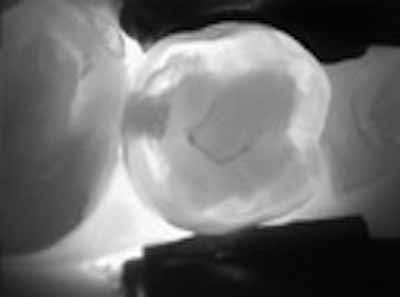

光ファイバーを使用すると、光(白色可視光を使用するFOTIおよびDiFOTI 、およびNIR光を使用するDIAGNOcam)を集中させ、歯の咀嚼面と接触領域を照らすことができます。歯の脱灰した部分、つまりう蝕病変は、黒い斑点として見えます。この方法は、虫歯であるか否かという定性的な回答を提供し、視覚的・触覚的検査を補完するものとして使用することができます。 DiFOTIおよびDIAGNOcam機器はFOTIと同じ原理に基づいていますが、デジタルマイクロビデオカメラも含まれており、画像を保存して次回の検査で比較することができます(画像5)。